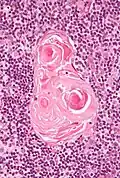

Na medula, a rede de células epiteliais é mais grossa do que no córtex, e as células linfóides são relativamente menores em número.[2] Corpos concêntricos semelhantes a ninhos chamados corpúsculos de Hassall (também chamados corpúsculos tímicos) são formados por agregações das células epiteliais medulares.[4] São espirais concêntricas e em camadas de células epiteliais que aumentam em número ao longo da vida.[2] São os restos dos tubos epiteliais, que crescem a partir das terceiras bolsas faríngeas do embrião para formar o timo.[6]

Micrografia mostrando o corpúsculo de Hassall, encontrado na medula do timo.